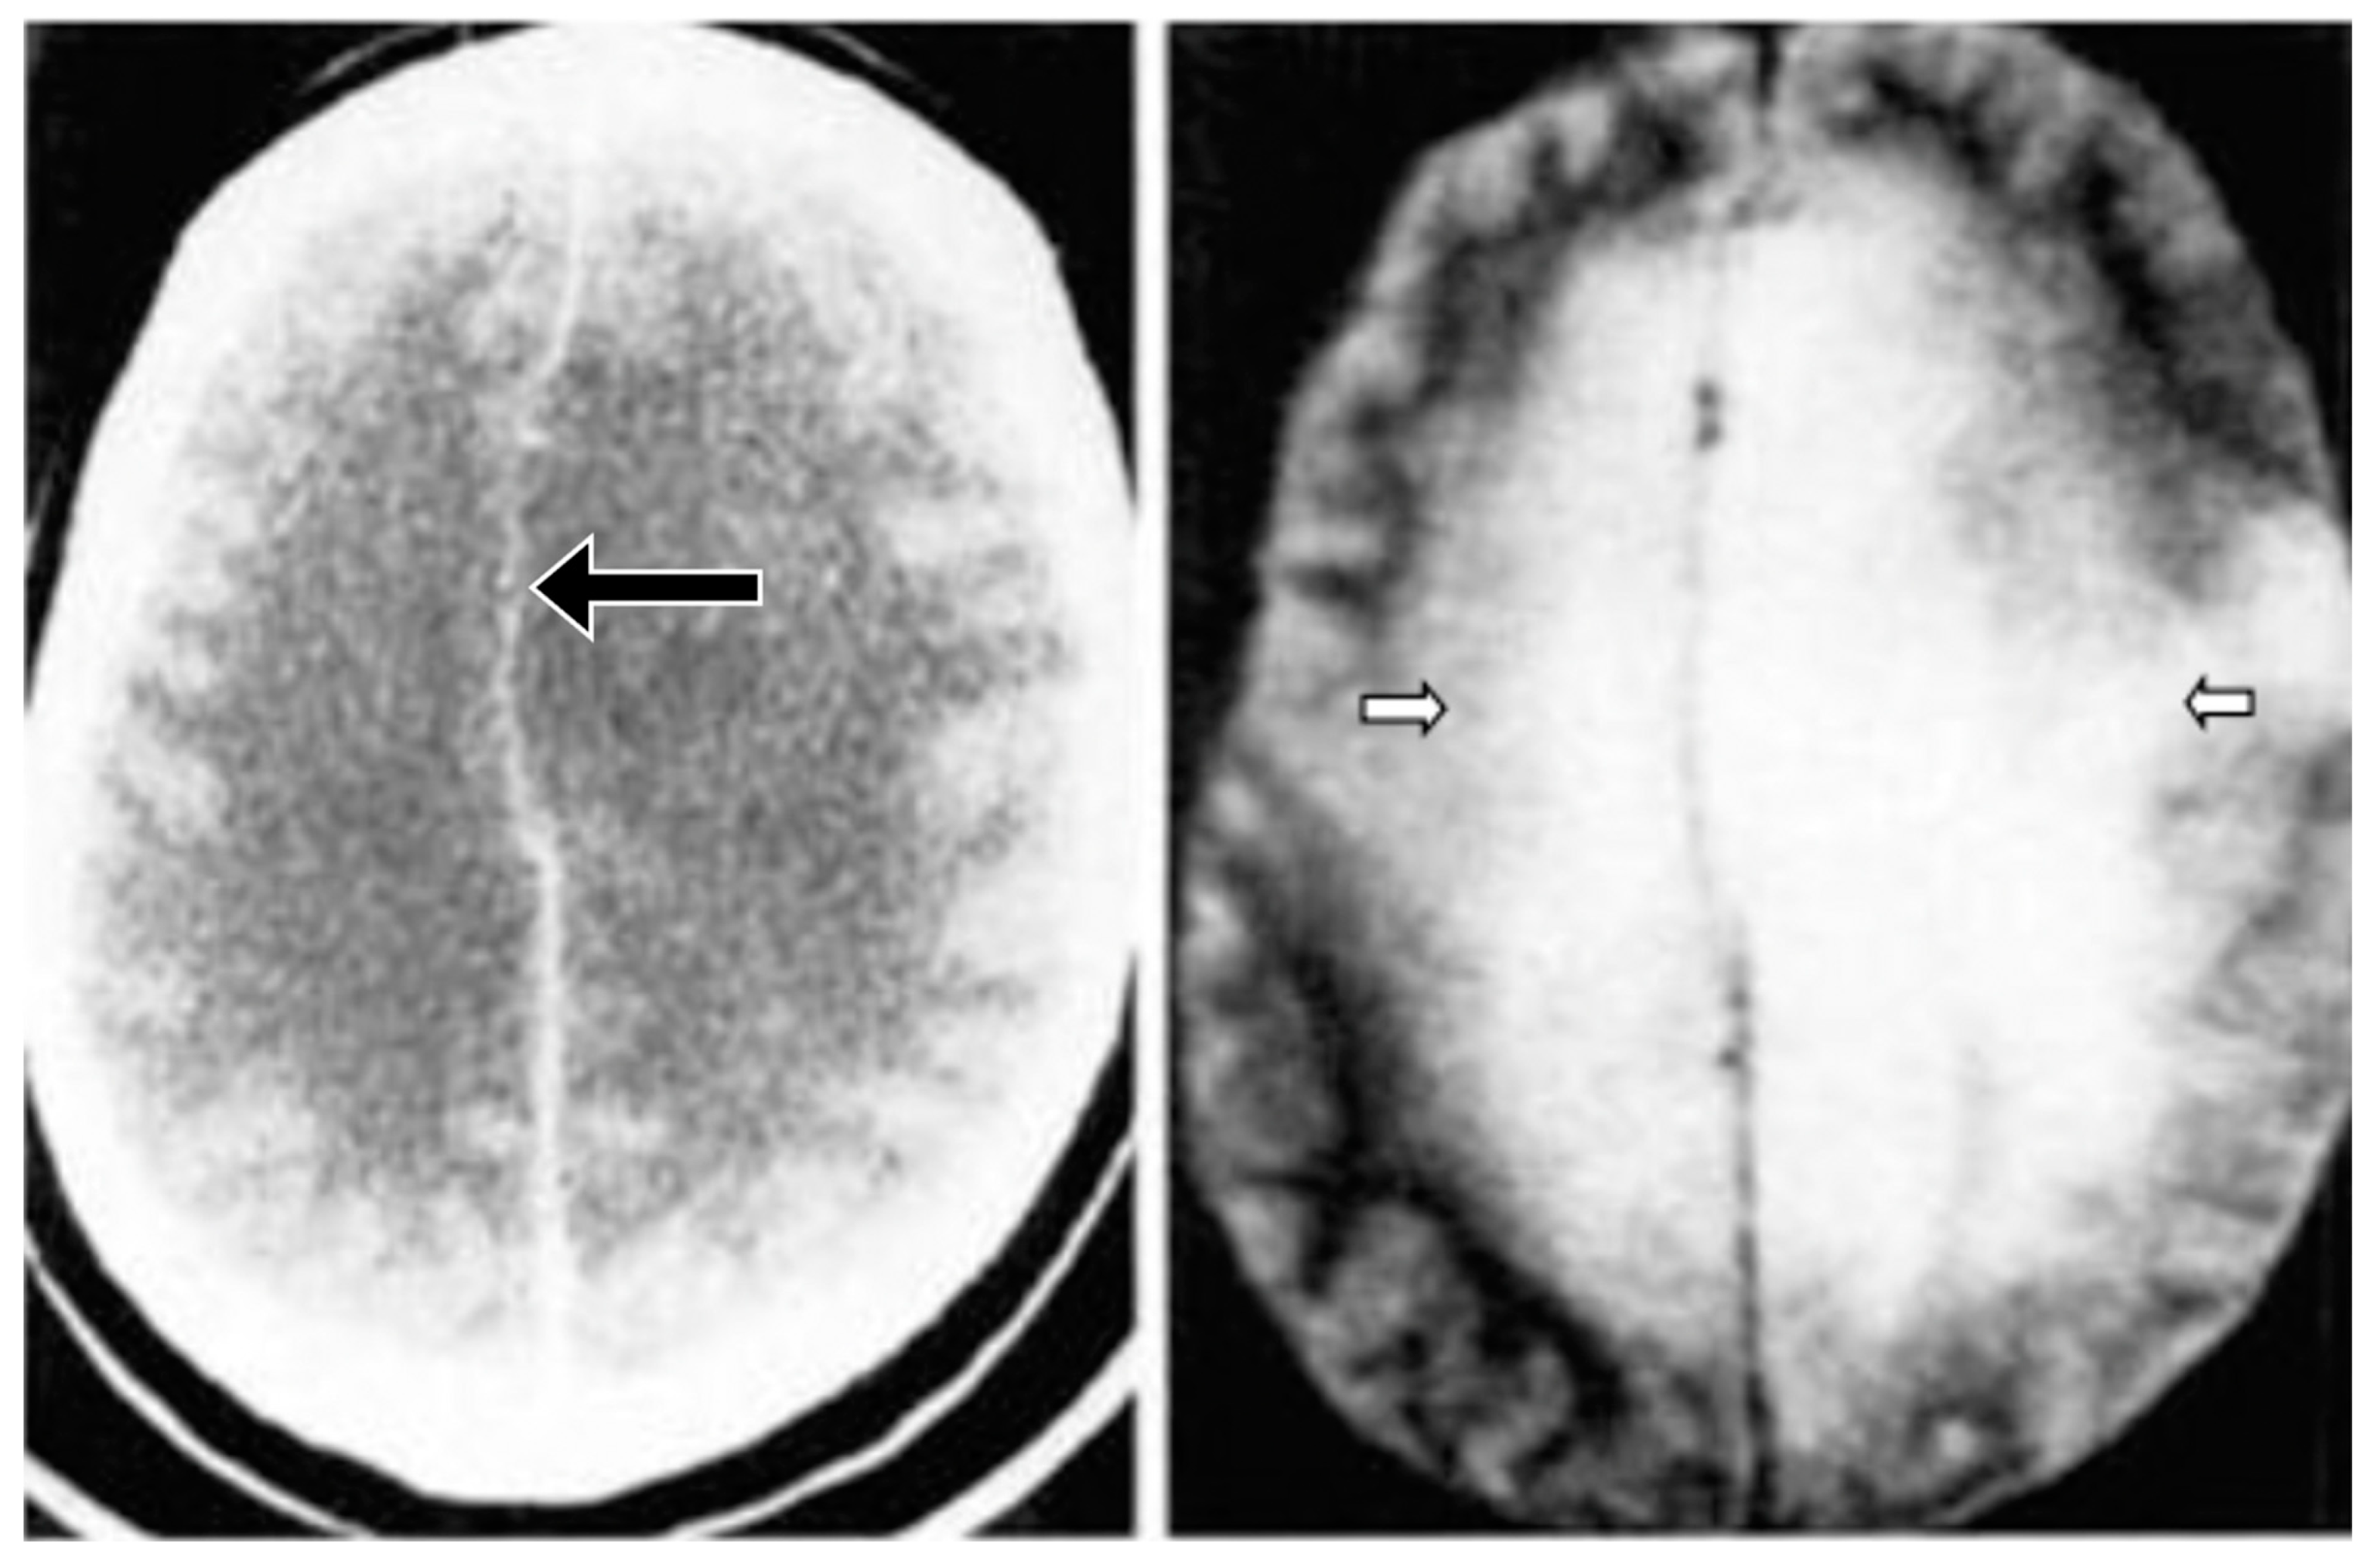

Figure 18 compares T2-FLAIR images (left column) with matched narrow mD dSIR images (right column) in Case 1 at the time of his first examination. No abnormality is seen in the white matter on the T2-FLAIR images (left column) but extensive high signal abnormalities are seen in white matter on the narrow mD dSIR images. Small areas of more normal white matter with a low signal appearance are shown by the white arrows (right column). These are features of a whiteout sign grade 4.

Figure 18.

Case 1 patient with methamphetamine use disorder. Comparison of T2-FLAIR and narrow mD dSIR images. No abnormality is seen on the T2-FLAIR images (left column) but there are extensive areas of higher signal in approximately 90% of the white matter (right column). Only small areas of normal low signal are seen in the white matter (white arrows) (right column). The appearances on the dSIR images are consistent with a whiteout sign grade 4.